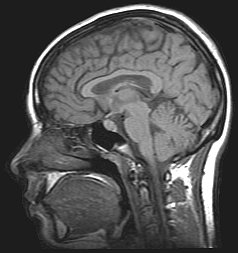

From the earliest days of neuroanatomy, experts have tried to explain the differences between males and females. Clearly, behavior originates in the brain, so the assumption was that there must be structural differences among the some 86 billion neurons that make up the typical human brain that explain the behavioral differences between the genders. But search as they might, they never found one. Despite this failure, this assumption has continued to prove remarkably durable over the centuries.

In a consistently conversational tone, Rippon explores much of this history, revealing how stubbornly gender bias has permeated neurological science. From the most rudimentary early skull measurements to the current heyday of functional MRI, scientists have measured, assayed, dissected and tested countless brains in an effort to determine why girls like flowers and boys like trucks. Surely, an explanation must be hiding in there somewhere.

Exhaustively combing through vast numbers of studies – and sharing a lot of fun details about how psychologists unmask the brain’s many secrets along the way – Rippon eventually reveals that our brains really aren’t gendered after all. Maybe not even a little bit. But our life experiences are gendered from the very first moment. And that makes all the difference. It’s a rather astounding premise, but the author’s argument is rock solid and makes for very enlightening reading.

I studied neuroanatomy in school (quite a few) years ago, but while I didn’t realize it at the time, one thing that was missing in our lectures was any suggestion of where the girl and boy parts of the brain were located. In hindsight – and certainly after reading Gender and Our Brains – I’ve come to the realization that the concept of male and female brain parts makes about as much sense as the idea of male and female kidneys. And while that’s interesting all on its own, it’s crucial to recognize the significance that this modern and evidence based approach to gender has on society around us. Rippon doesn’t hesitate to do that throughout this important work, repeatedly encouraging everyone to shed their equally ubiquitous and tenacious stereotypes as we enter a brave new world of gender enlightenment. Highly recommended.